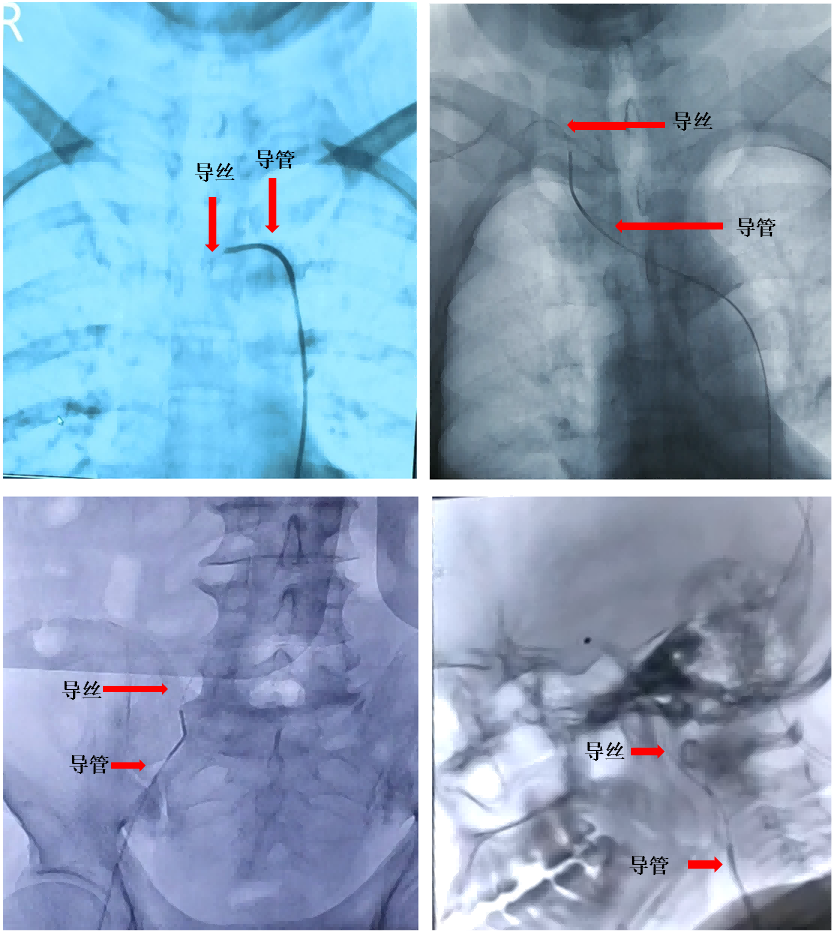

2019年11月在北京天坛医院

完成国内首例全脑血管临床试验

2019年11月

该手术机器人系统成功实施

国内首例全脑血管临床试验

医生遥控机器人操作导管、导丝

沿腹主动脉、主动脉弓、

颈总动脉、颈内动脉等

进入患者相应区域进行造影

手术获得成功